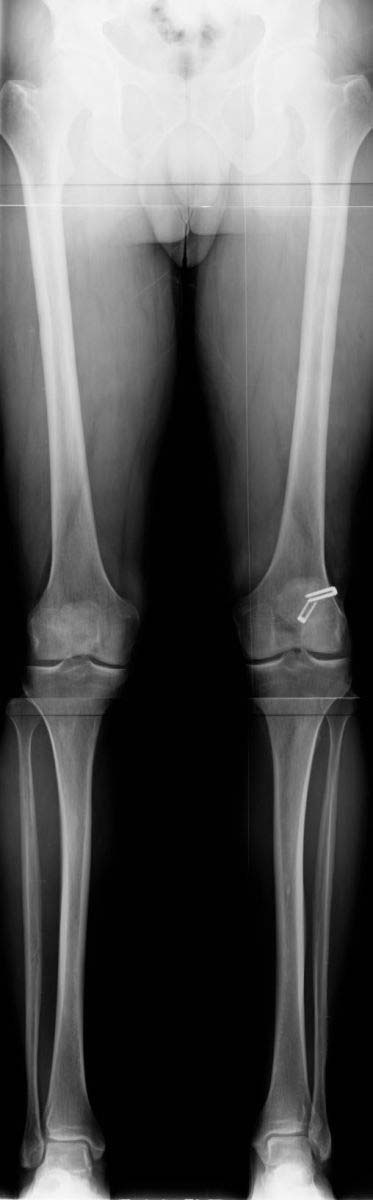

2.Standing alignment radiographs are routinely obtained. These demonstrate a mechanical and anatomical alignment that is within the normal range eliminating the need for corrective osteotomy.